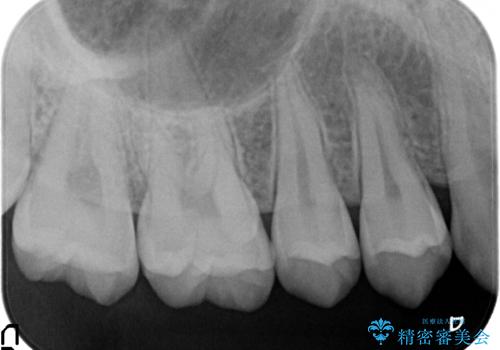

検診による初期虫歯の早期発見・早期治療

- 検診を希望され来院されました。

症状は特にありませんでしたが、検診で全体をチェックすることで虫歯を小さなうちに早期発見し治療することができました。

- 7万円 (emaxインレー)費用は治療当時の料金となります